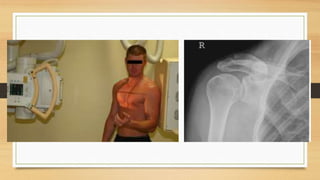

1. RADIOGRAFIA: SERIE TRAUMATICA: AP

EXAMENES DIAGNOSTICOS 1. RADIOGRAFIA:SERIE TRAUMATICA: AP CORREGIDA, ESCAPULAR EN Y Y AXILA 2. TAC 3D